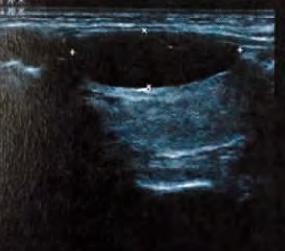

查体:左甲状腺可触及一直径2cm结节,质中,两结节均边界清楚,随吞咽上下活动。余查体未见明显异常。 辅助检查:血尿常规、肝肾功未见明显异常。B超:双侧甲状腺回声均匀,左甲状腺上方探及一大小2。5cm×1.0cm 囊性包块:彩超:左甲状腺包块内未见明显血流信号。